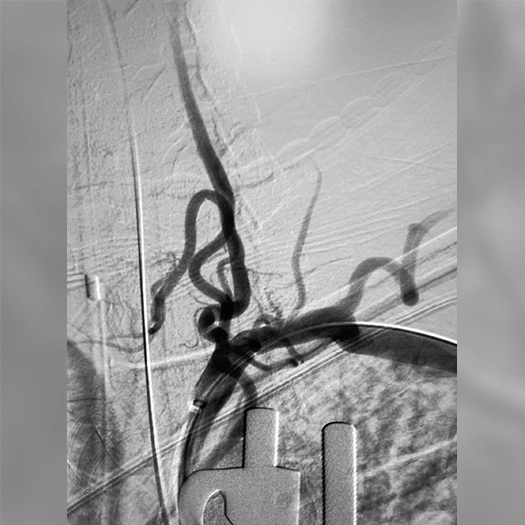

angiogram of a fistula

Direct CC fistula managed with two complex coils and SwiftPAC: 60 cm, 30 cm, 15 cm

CC Fistula

• PC400 and SwiftPAC designed for complex fistulas

• Offered high volume, flexible design, and embolization

• BENCHMARK family is designed to facilitate the therapy of a wide range of conditions